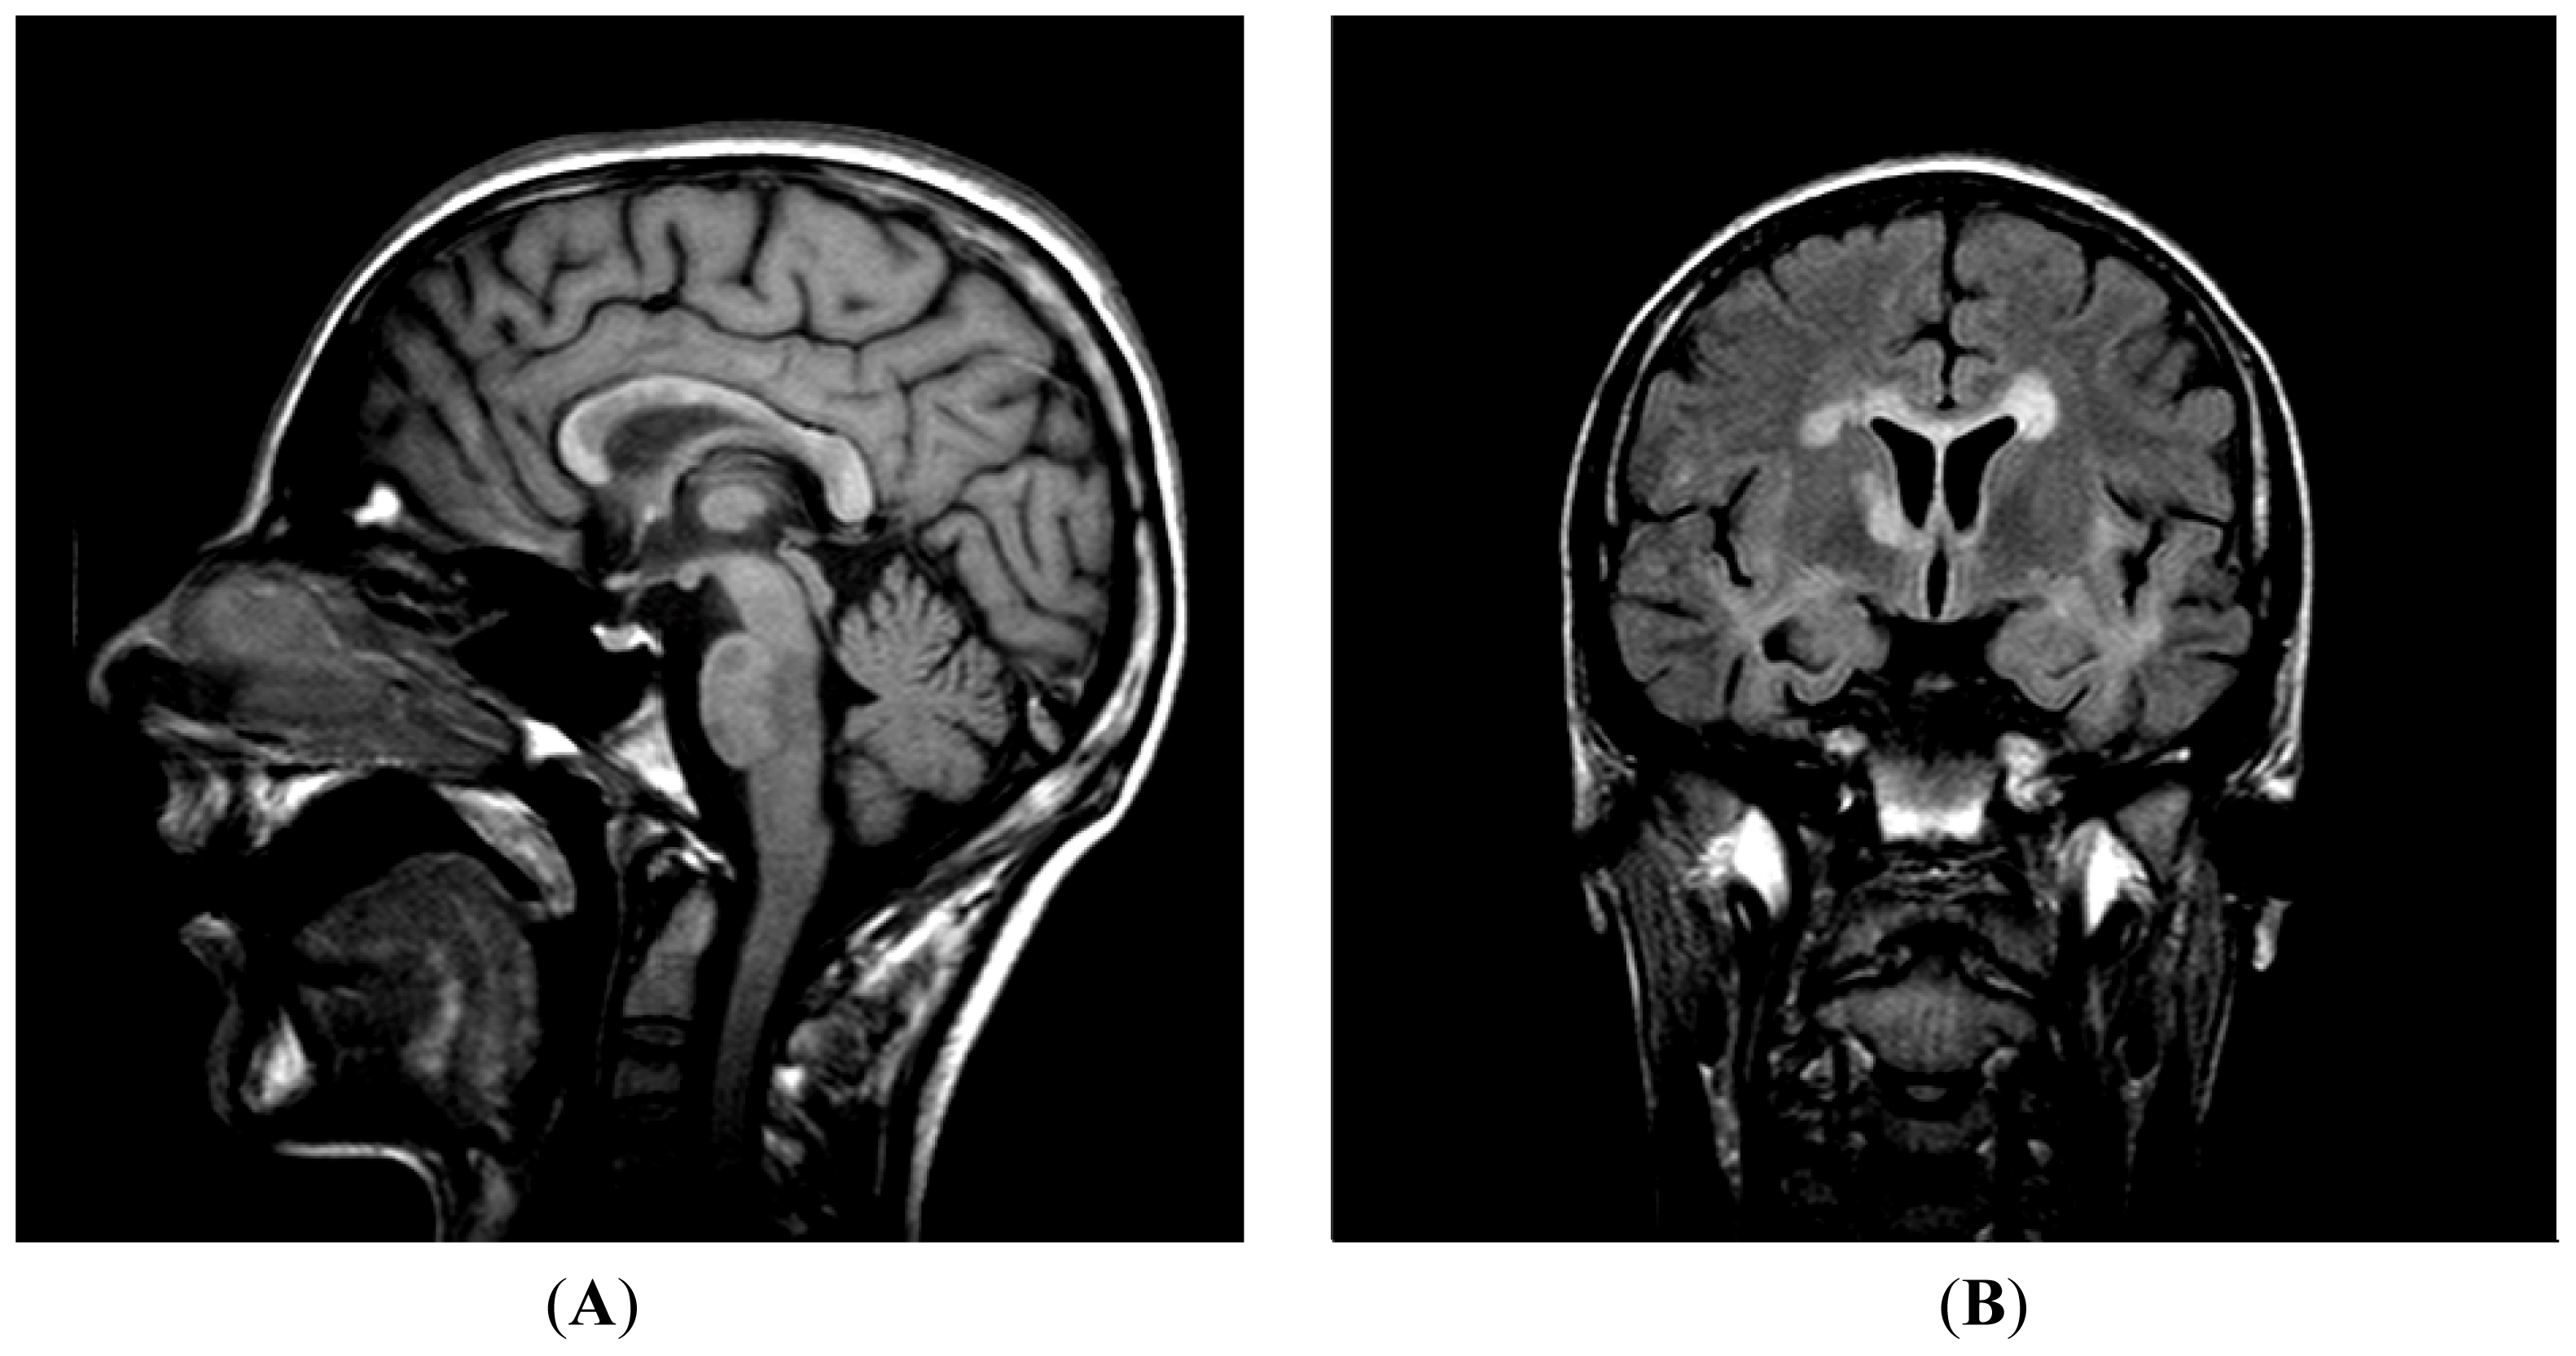

4.1. Patient Case History and Outcome

4.1.1. Examinations